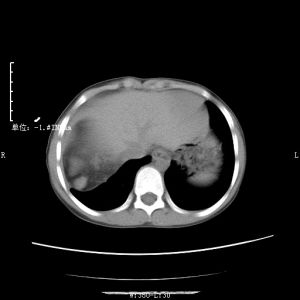

(3)CT檢查如果病變巨大,甚至占據腹腔的4/5,則多個臟器受壓移位。病變的內部結構紊亂,密度不均,呈混合性密影,亦可為實性和囊性成分組成。